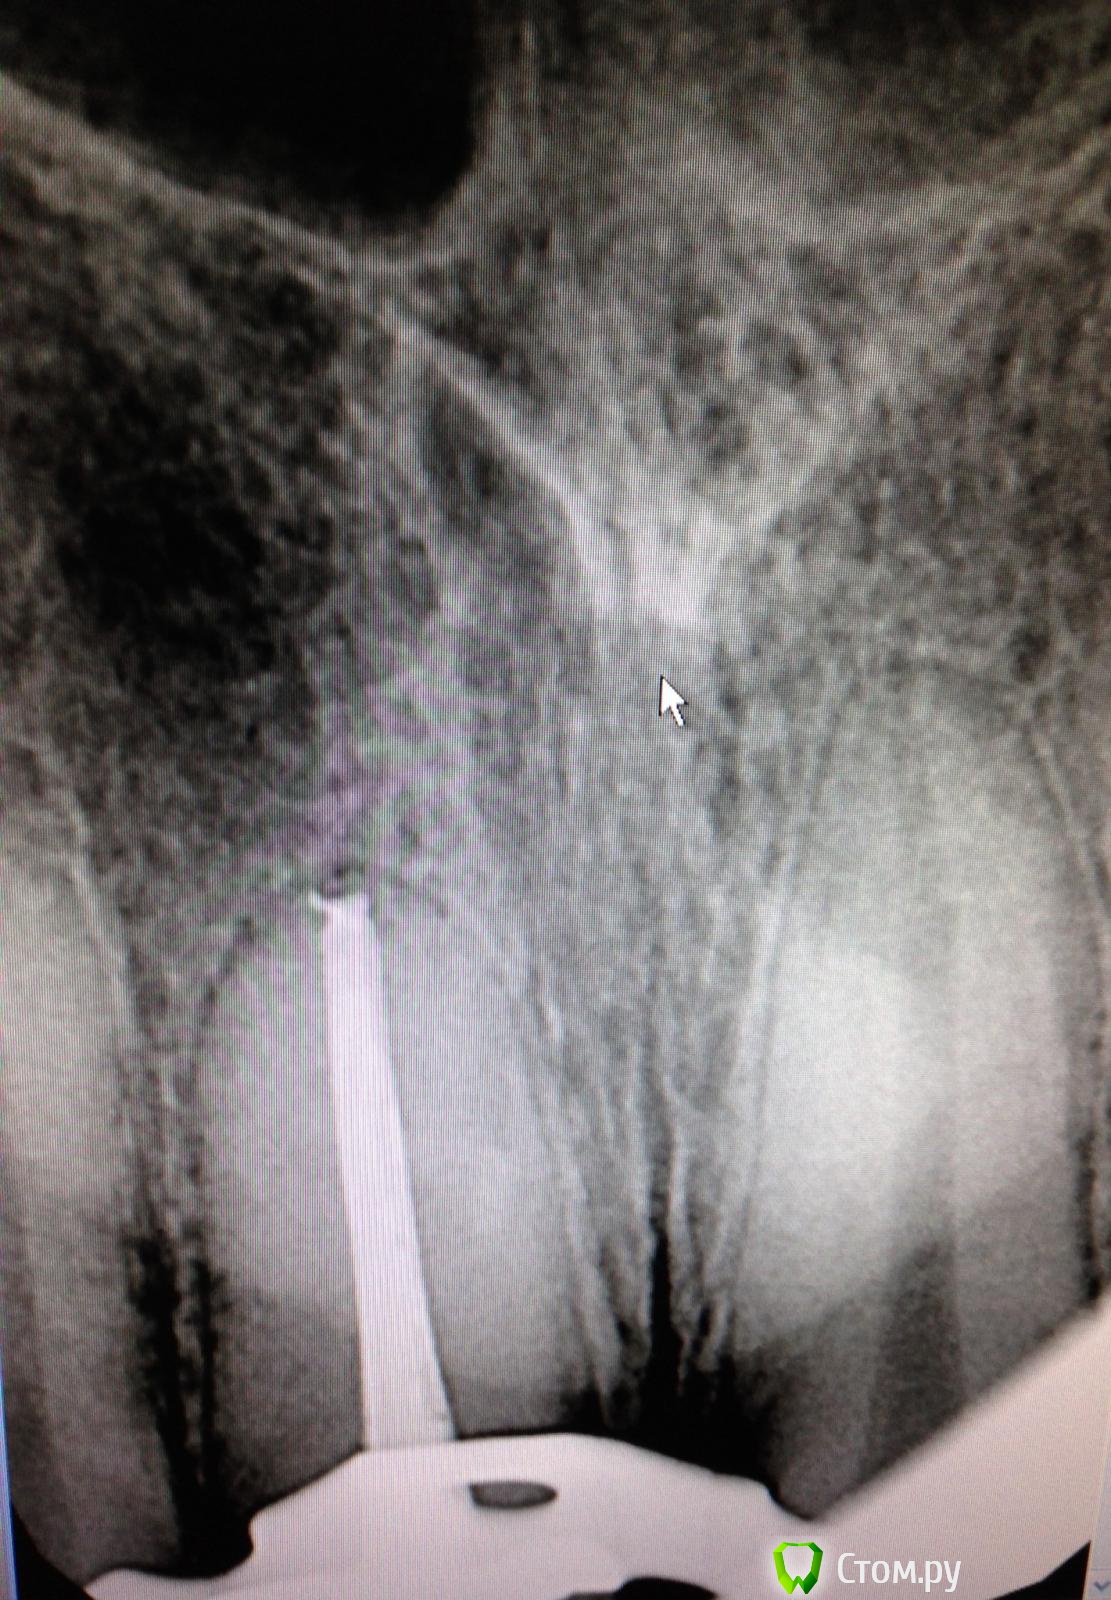

SSTi Опубликовано 6 сентября, 2014 Автор Поделиться Опубликовано 6 сентября, 2014 (изменено) Новая история.Пациент молодой.4 резца вч.12 периодонтит. 11 кариес дентина. 21, 22 - периодонтитСитуация до1 посещение. Анестезия 1.7 в области 21-22. Коффер. Преп. Обработка каналов. Ирригация. Кальций. Временная.2 посещение. Анестезия в области 11 ,12, 21 ,22. Коффер. Преп и реставрация 11.Преп, обработка и ирригация 12, паковка.Ирригация 21-22. При пошружении файла в каналы 21 и 22 - боль за 3-4 мм до апекса. Не кровит. Обработка была в пределах разумного(ленточное перфо не мог натереть). Идем на снимокБоль на этом уровне. Причем при введении мастер штифта боль есть. Если ввожу 15-20 аккуратно - боли нет. Добавляем анестезию. Аккуратно удается запломбировать 22.21 - боль осталась. Оставил кальций.На корнях 22 и 21 в боковом отделе есть разрежения небольшие. Боль примерно на их уровне. Но это вряд ли связано думаю. (Это латерали?).Вопрос. Какова причина боли? Склоняюсь к анестезии. Такое чувство, что повторно плохо взяла(посещения рядом по времени).+ слизистая вобл 21 была слабочувствительна Изменено 6 сентября, 2014 пользователем SSTi Ссылка на комментарий